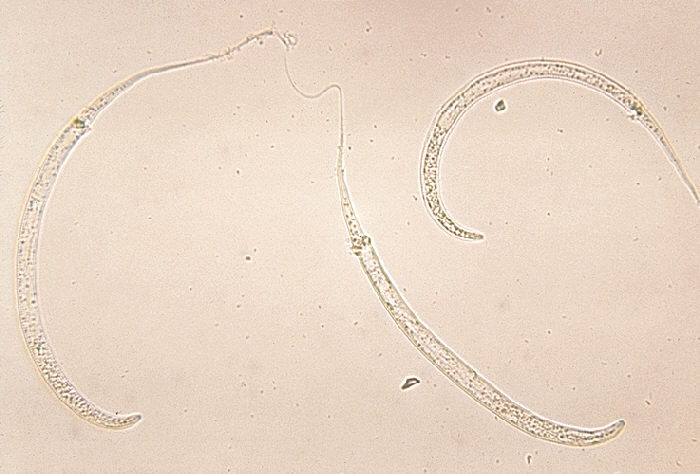

Species

Dracunculus medinensis

Common:dracunculiasis worm, Guinea worm disease nematode (German: Medinawurm, Guineawurm)